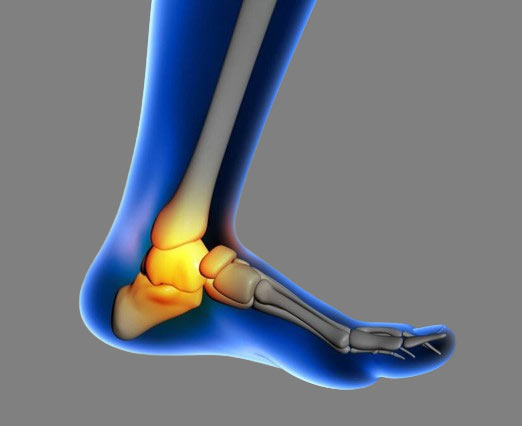

발꿈치뼈라고 부르는 종골 착지할 때 체중이 발꿈치 쪽으로 집중이 되기 쉽죠. 따라서 낙상사고로 다치는 경우가 대부분이에요. 또한 교통사고시 페달과 바닥에 의해 발에 큰 충격이 가해지면서 부상을 입기도 합니다.

종골은 그 자체가 굵고 튼튼해요. 하지만 한 번 다치면 치료도 쉽지 않고 통증 등으로 불편함이 지속되는 경우가 많아요. 체중의 부하를 많이 받는 곳이기 때문에 부상 이후에는 걷는 것부터 무리가 뒤따르곤 합니다.

종골의 위치상 신체의 무게를 전달받을 수 밖에 없죠. 따라서 이렇게 치료를 잘 받더라도 일상생활에 상당한 제약이 생깁니다. 보행상의 장해, 발목 관절의 운동장해 등 여러 후유증이 남게 되는데요 의뢰인 역시 원상태로의 완전한 회복이 어려웠습니다.